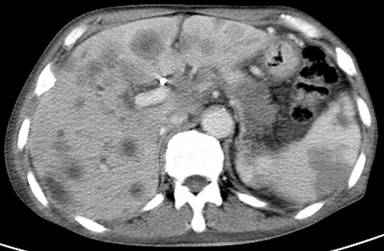

A sixty-eight-year-old male patient with a history of smoking (40 packs/year) without known cardiovascular disease was admitted to hospital. He was complaining of fatigue, dyspepsia, epigastric pain, weight loss of 10 kg over the previous month and also swelling, pain and hyperemia in left leg. Acute thrombosis was detected in the left main, deep and superficial femoral veins and popliteal vein at venous Doppler ultrasound. An upper gastroendoscopy revealed pangastritis and external compression of antrum. Multiple solid lesions greater than 1 cm in size were detected in abdominal ultrasonography and considered as prospective metastatic lesions. Abdominal computed tomography demonstrated a 4.5x2.5 cm mass in the tail of pancreas (Figure 1). Laboratory investigations revealed elevated CEA (5 ng/mL), CA 19-9 (>1,000 U/mL) and protrombin time (16 sec) levels with mild thrombocytopenia (130,000 109/L) and an increased D-dimer (4 µg/mL (conventional units)). Percutaneous liver biopsy was performed on the lesion. Full dose LMWH treatment was initiated immediately following liver biopsy. Liver histology confirmed adenocarcinoma with morphology consistent with pancreatic primary. Stage IV pancreatic cancer with thrombotic complications was suggested. Chemotherapy was initiated as gemcitabine 1,000 mg/m2 day 1 and day 8, carboplatin AUC5 day 1 per three weeks. Seven days after the initiation of chemotherapy, the patient presented with hematemesis, thrombocytopenia (43,000/µL) and a prolonged PT (16 sec) and he was hospitalized. Thrombocytopenia was initially considered to be secondary to chemotherapy. On physical examination, coolness, pallor and decreased pulse in right lower extremity were detected and arterial and venous Doppler ultrasonography was performed on both legs (Figures 2 and 3). Subacute thrombosis was detected in the left main, superficial, profound femoral veins and popliteal vein and thrombi causing obstruction of the right main femoral, popliteal and posterior tibial arteries. LMWH could not be given because of hematemesis and thrombocytopenia. Surgical intervention for arterial thrombi was not considered due to rapid deterioration of the patient's status. Thrombocytopenia got worse and the patient received thrombocyte concentrate and plasma. The patient's orientation in time and space broke down during the follow-up. Ten days after hospitalisation, thrombocytopenia worsened, PT got prolonged, fibrinogen levels increased to 310 g/L and D-dimer was also elevated (15 µg/mL). Hepatic and renal failure developed. Peripheral blood smear revealed findings compatible with microangiopathic hemolytic anemia (schistocytes). Evaluation of the patient according to ISTH criteria suggested overt DIC with a score of 8. Differential diagnoses included liver failure secondary to metastases, other microangiopathic syndromes, anti-phospholipid syndrome, vitamin K deficiency and these were excluded according to clinical and laboratory findings. The patient passed away 2 months after the diagnosis.

Figure 1. Abdominal computed tomography images showing a 4.5x2.5 cm mass in the tail of pancreas and multiple hepatic metastases. |